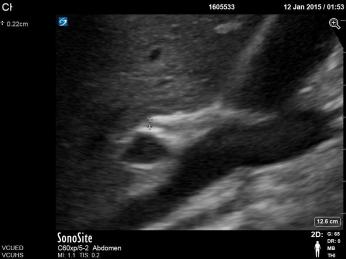

Biliary A. Clip of long axis of GB with portal triad https://vcuultrasound.com/wp-content/uploads/2020/07/0a613-video-8.1-gb-long-axis.mp4 B. Clip of scan through short axis of GB https://vcuultrasound.com/wp-content/uploads/2020/07/c6f26-video-8.2-gb-short-axis.mp4 C. Measurement of CBD with color flow (inner to inner wall) D. Measurement of GB wall in cross section at anterior portion from outer to inner Share this: Share on X (Opens in new window) X Share on Facebook (Opens in new window) Facebook Like Loading...